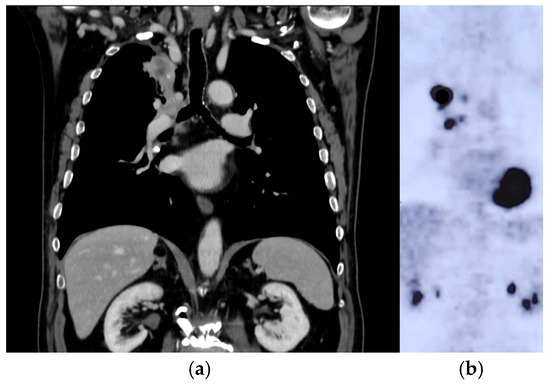

2. Case Report